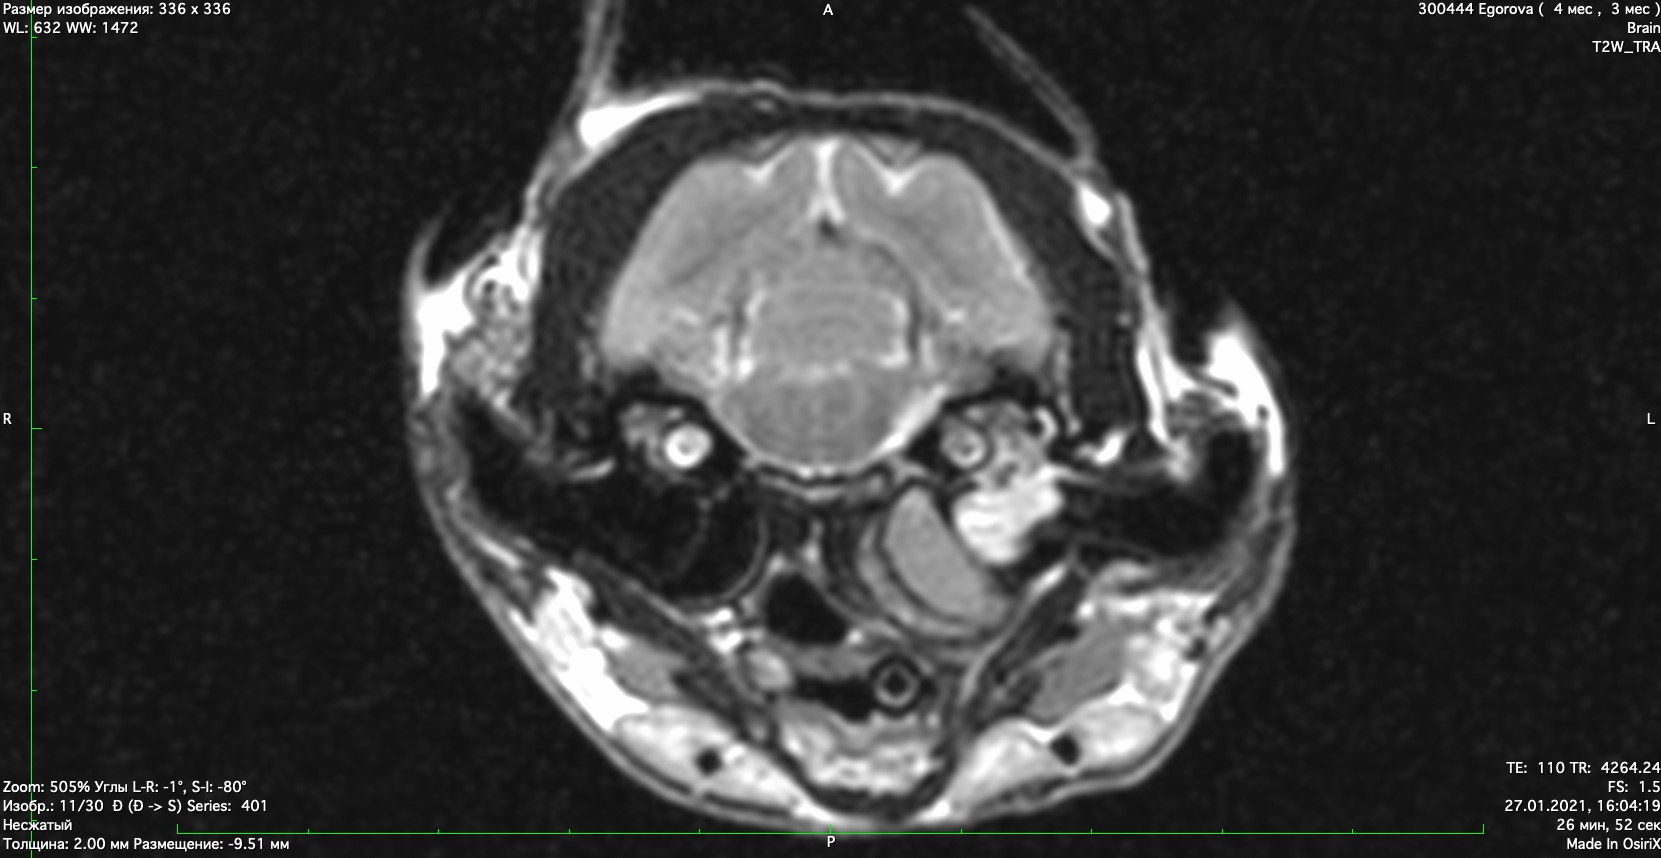

При проведении мрт диагностики установлено- признаки полипа в полости среднего уха, признаки гнойного содержимого в булле. Поставлен диагноз-полип, средний отит.